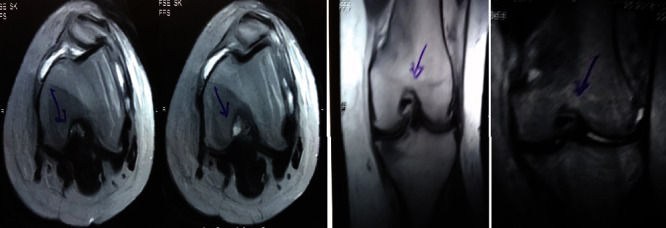

治療后一個(gè)月進(jìn)行隨訪。在第一次細(xì)胞治療后,患者的疼痛明顯減輕。第二次療程后,她沒(méi)有疼痛,并注意到運(yùn)動(dòng)范圍有所改善。持續(xù)的物理治療也觀察到下肢肌肉力量的增加。從治療開(kāi)始(11個(gè)月前)到最后一次隨訪(4個(gè)月前),患者按照建議的飲食和基于運(yùn)動(dòng)的方案減重了11公斤。因此,她現(xiàn)在整體身體健康,能夠更舒適地進(jìn)行日常生活活動(dòng)。表3顯示治療前后的MRI檢查結(jié)果。人物的圖1和的和圖2顯示半月板撕裂的治療前和治療后(1年后)圖片。觀察到損傷程度的改善圖2。